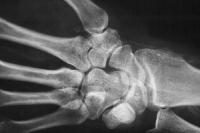

Appearance of the wrist and thumb after multiple debridements for progressive infected wound necrosis following failed radiocephalic shunt construction. The radial artery has been ligated.

By this point, the patient has undergone proximal row carpectomy for control of infection involving the scaphoid and lunate. The capitate is visible in the depths of the wound: